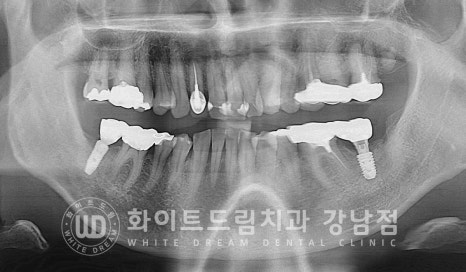

오스 soi 임플란트 5.0x8.5mm 식립 후 모습니다.

(강남역 임플란트재수술 치과 / 수술일자 : 23.10.26)

3개월의 임플란트가 새로운 뼈와 유착되는 시간을 가지면서

정상적으로 회복되고 있음을 확인한 후에 이제 임플란트 최종 보철 제작에 들어가게 됩니다.

▲ 이식재가 새로운 뼈로 생성되었고 임플란트와 단단하게 결합된 것이 확인됩니다.

동일 인물이며 동일 환경에서 촬영되었습니다.

강남역 임플란트재수술 치과 / 치료 기간 : 23.08.14 - 24.02.03